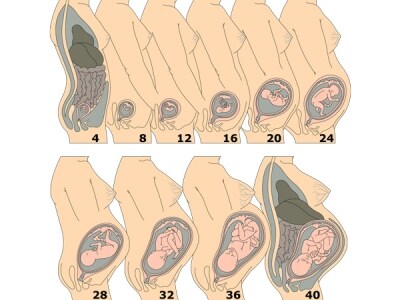

胸焼けは妊娠後期、特に 36 週以降に最もよく起こります。これは、妊娠の終わりに近づくにつれて、お腹にかかる胎児の圧力が高まるためです。

これは妊娠の第三期に最も蔓延しており、通常、赤ちゃんが出産前に最大の体重と大きさに達する妊娠 36 週以降に最も厄介になります。

これらの症状は、妊娠が進むにつれて、特に36 週に達すると悪化する可能性があります。妊娠 36 週の時点で、赤ちゃんの体重は約 6 ポンド、体長は約 18 インチで、今後数週間で急速に成長し続けます。妊娠40週までに、赤ちゃんの体重は7〜8ポンド、体長は約20インチになります。それは胃や消化器系に大きな負担がかかります。